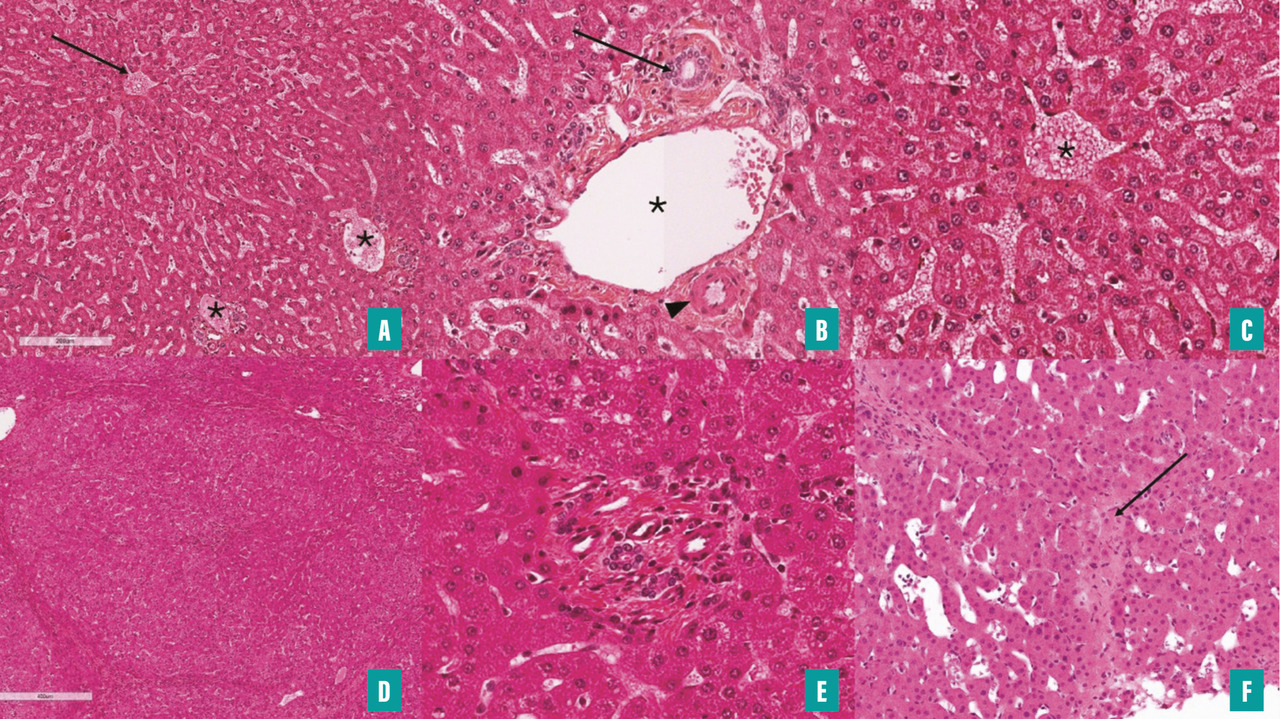

L’évaluation histologique de la biopsie hépatique repose sur l’analyse de coupes sériées. La coloration standard à l’hématoxyline-éosine (HE) ou à l’hématoxyline-éosine-safran (HES) permet d’étudier la plupart des caractéristiques histologiques  ; une coloration du tissu conjonctif (coloration de Picro-Sirius ou trichrome de Masson) est également réalisée. La coloration de la réticuline fournit une évaluation plus précise de l’architecture hépatique que l’HE/HES, ce qui est particulièrement utile pour mettre en évidence les processus de régénération dans un contexte de maladie vasculaire.

L’interprétation de la biopsie hépatique repose, comme pour les autres maladies du foie, sur une analyse systématique des différentes structures morphologiques du foie, avec une attention spécifique pour les espaces portes et en particulier les veines portes, les veines centrolobulaires et les sinusoïdes (voir critères analysés dans la figure 4).10 En particulier, une atteinte des veines portes et des sinusoïdes fait discuter une maladie vasculaire porto-sinusoïdale tandis qu’une atteinte des veines centrales et des sinusoïdes fait évoquer les diagnostics de syndrome de Budd-Chiari ou encore de syndrome d’obstruction sinusoïdale (fig. 5).